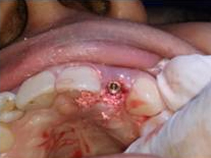

Drilled socket for Implant

Single Tooth Implant

Punch Cut

Placement of Bone Grafting

After Punch Cut